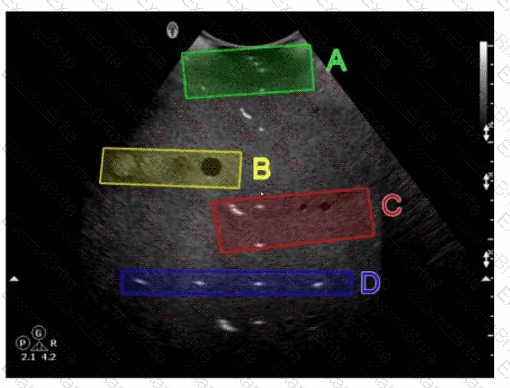

Questions 18

Which target group is used to evaluate transverse distance measurement accuracy in this tissue-mimicking phantom image?

Options:

A.

Option A

B.

Option B

C.

Option C

D.

Option D

Discussion 0